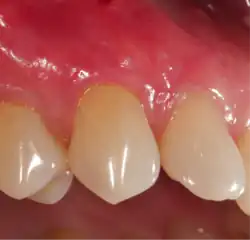

In periodontology, gingival grafting, also called gum grafting or periodontal plastic surgery,[1][2] is a generic term for the performance of any of a number of surgical procedures in which the gingiva (gum tissue) is grafted. The aim may be to cover exposed root surfaces or merely to augment the band of keratinized tissue.

Gum grafting, also known as a gingival graft or periodontal plastic surgery, is a surgical procedure to reverse gum recession. Gum recession exposes the roots of teeth,[9] which can lead to sensitivity and put teeth at a higher risk of damage or disease[10] due to the loosening of their attachment within the gums and bones of the jaw. Should gum recession continue, bone and keratinized tissue will be at greater risk of being damaged and permanently lost around the teeth. The aim of a gum graft is to extend keratinized tissue of the gums to cover tooth roots,[11] which restores their firm placement within the jaw and prevents further damage.